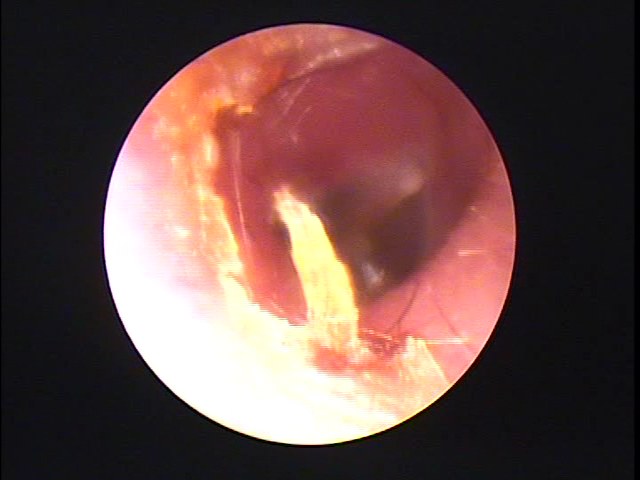

耳について | 千葉耳鼻咽喉科クリニック from chibacl.com